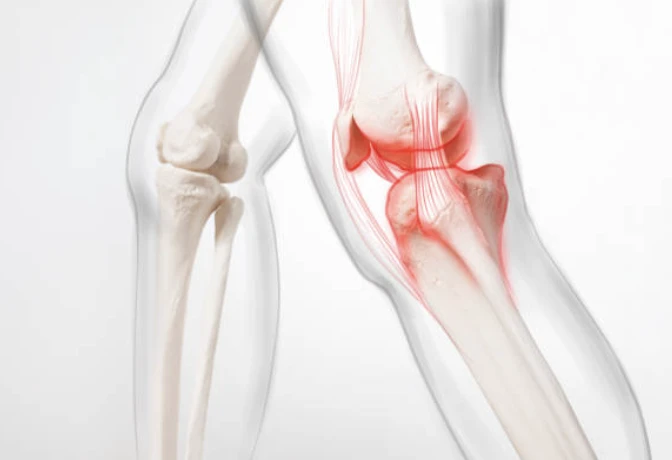

무릎의 구조

무릎이 어떤 부분으로 구성되어있는지 간략하게 살펴보겠습니다. 무릎은 들어 올리기, 무릎 꿇기 등의 일상적인 활동과 걷기 및 달리기, 에어로빅과 같은 고강도 활동으로 인해 많은 스트레스를 받는 취약한 관절입니다. 무릎 통증 원인은 이유가 다양할 수 있습니다.

각 뼈의 끝은 충격을 흡수하기 위해 연골층이 덮여있습니다. 기본적으로 무릎은 근육과 인대 그리고 힘줄에 의해 결합된 2개의 다리뼈입니다.

무릎에는 다리를 곧게 펴는 대퇴사두근(허벅지 앞쪽에 위치)과 다리를 구부리는 햄스트링 근육(허벅지 뒤쪽에 위치)을 포함하고 있습니다.

힘줄은 근육과 뼈를 연결하는 질긴 조직입니다. 인대는 뼈와 뼈를 연결하는 조직의 탄성 밴드와 같은 역할을 합니다. 무릎의 일부 인대는 관절의 안정성과 보호를 제공하지만, 다른 인대는 정강이 뼈의 앞뒤 움직임을 제한합니다.

- 염좌 또는 긴장된 무릎 인대와 근육은 일반적으로 무릎에 대한 타격이나 무릎의 갑작스러운 비틀림으로 인해 발생합니다. 해당 증상으로는 통증, 붓기, 움직이지 못함 등이 있습니다.

- 무릎 연골 손상은 무릎 외상으로 인해 반월판(충격 흡수제 역할)이 찢어지는 것입니다. 연골 파열은 종종 염좌와 함께 발생할 수 있는데, 치료방법에는 추가 부상으로 부터 무릎을 보호해 줄 무릎보호대를 착용하는 것이 포함됩니다.

- 무릎 힘줄 파열은 달리기, 점프, 자전거 타기와 같은 특정 활동 중에 힘줄을 과도하게 사용하여 발생할 수 있습니다. 또한 농구와 같은 점프를 자주 하는 스포츠에서도 주로 발생하는데, 정프를 위해 땅을 치는 힘이 힘줄에 부담을 줍니다.

- 관절염은 무릎에 영향을 미치는 가장 흔한 질병입니다. 골관절염은 관절의 연골이 서서히 마모되는 퇴행성 과정입니다. 이는 종종 중년 및 노인에게 쉽게 영향을 끼칩니다. 관절염은 반복적인 부상이나 과체중으로 인한 관절 스트레스 발생할 수 있습니다.